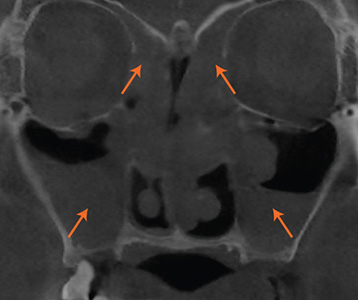

재수술 전